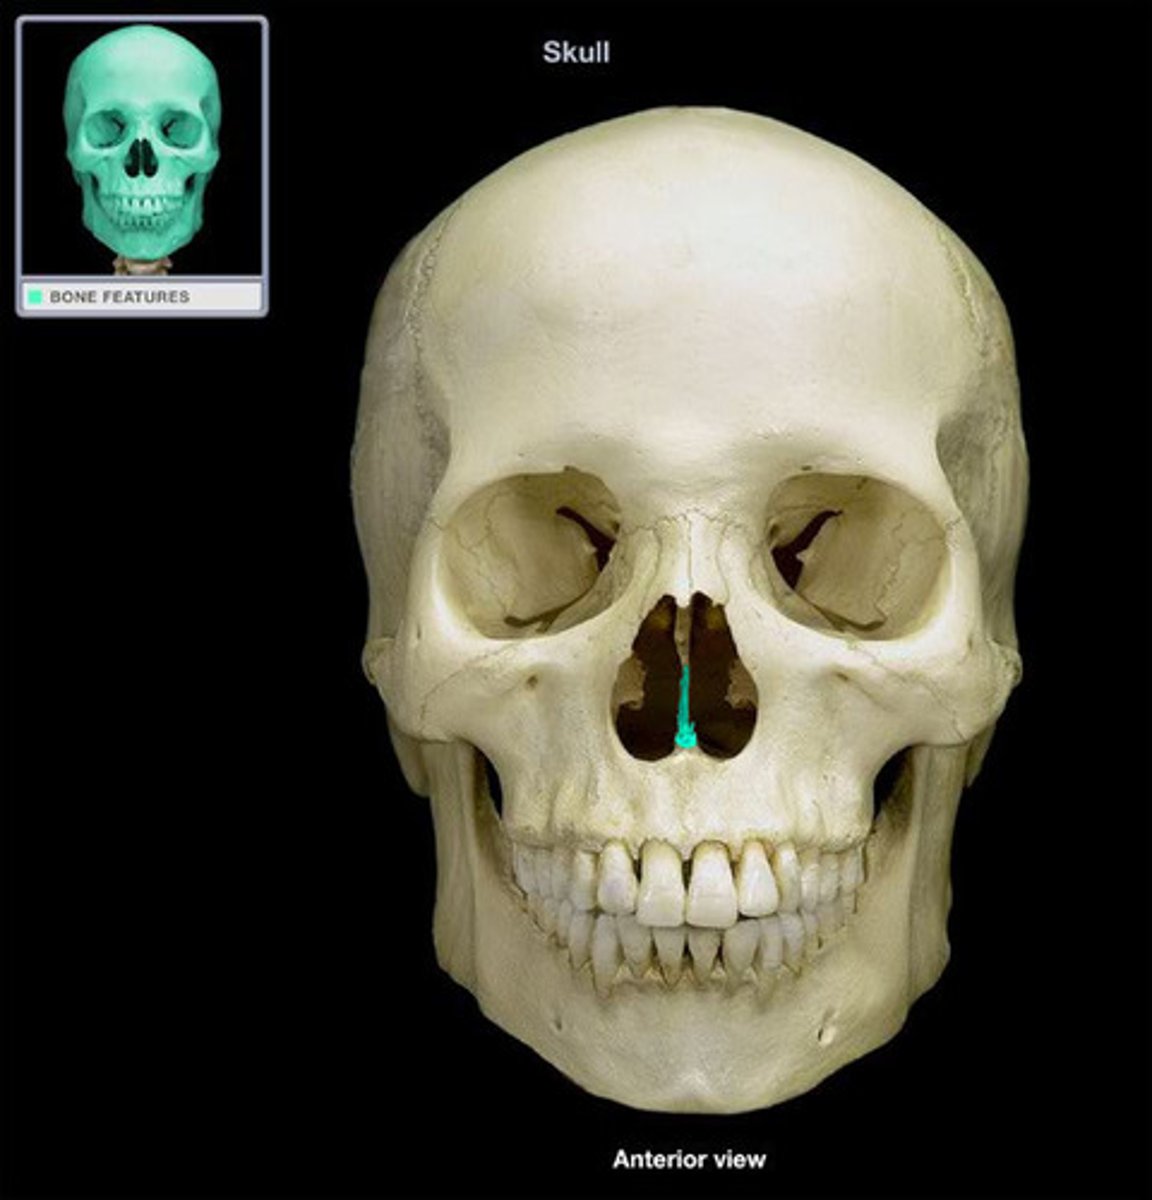

Cranium anatomy

frontal bone

frontal eminences

supraorbital margins

Supercilliary arches

supraorbital foramina

glabella

Ethmoid bone

ethmoidal notch

orbital plate

cribriform plate

crista galli

Name this bony landmark.

perpendicular plate

labyrinths

parietal bone

parietal eminence

sphenoid bone

lesser wings

greater wings

pterygoid processes

sella turcica

nasal bones

lacrimal bones

maxillary bones

zygomatic process of maxilla

maxillary sinus

infraorbital foramen

alveolar process of maxilla

anterior nasal spine

acanthion

zygomatic bone

temporal process of zygomatic bone

zygomatic arch

vomer

vomer